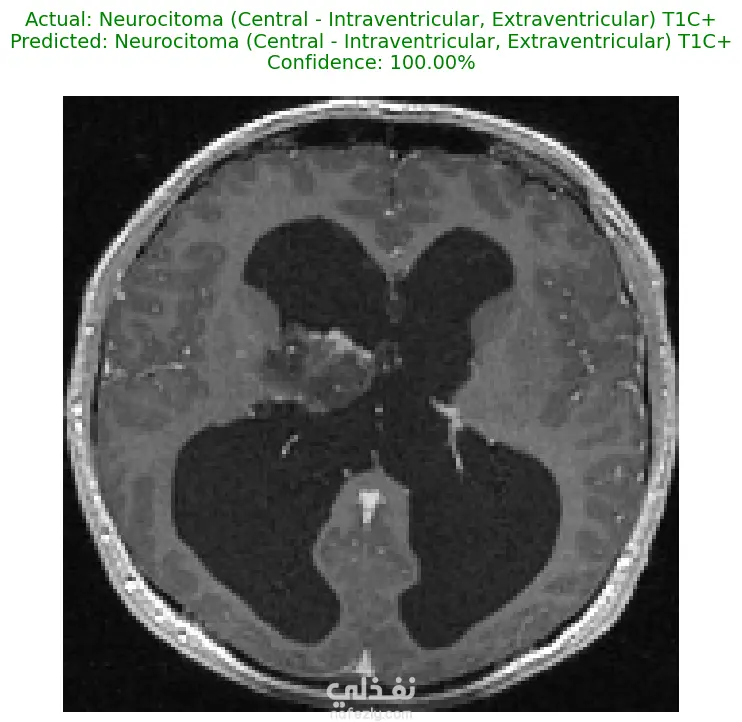

الوصف: قمت بتطوير نموذج تعلم عميق (CNN) قادر على التمييز بين 27 فئة مختلفة من الأورام والحالات الطبيعية بدقة تصل إلى 93%. شمل المشروع مراحل معالجة البيانات الضخمة، تنظيفها وموازنتها، وتصميم معمارية مخصصة لضمان الكفاءة العالية وتقليل استهلاك الذاكرة. المميزات التقنية: دقة استثنائية: حقق النموذج دقة تصل إلى 93% على بيانات التحقق (Validation Accuracy). معالجة البيانات الضخمة: تم العمل على قاعدة بيانات ضخمة، مع تطبيق استراتيجيات موازنة البيانات (Data Balancing) لضمان عدم انحياز الموديل. معمارية مخصصة: تم تصميم شبكة CNN تدعم تقنيات Batch Normalization لتسريع التعلم و Global Average Pooling لتقليل استهلاك الذاكرة وضمان استقرار النموذج. معالجة الصور: استخدام تقنيات OpenCV لقص الصور (Cropping) وإزالة الهوامش غير الضرورية لتركيز الموديل على منطقة الورم فقط. الأدوات والتقنيات المستخدمة: لغة البرمجة: Python. المكتبات الأساسية: TensorFlow / Keras. معالجة الصور: OpenCV & PIL. تحليل النتائج: Scikit-learn (Confusion Matrix & Classification Report). البيئة البرمجية: Google Colab (GPU Acceleration). النتائج المحققة: نموذج قادر على التعرف على أنواع نادرة من الأورام بدقة عالية. تقرير فني يوضح أداء الموديل لكل فئة (Precision & Recall). ملف نموذج جاهز للنشر (Deployment) بصيغة keras الحديثة. يمكنكم الاطلاع على الكود المصدري كاملاً والرسوم البيانية لتقييم أداء النموذج عبر رابط GitHub المرفق، كما يتوفر رابط تحميل النموذج المدرب داخل ملف الشرح.